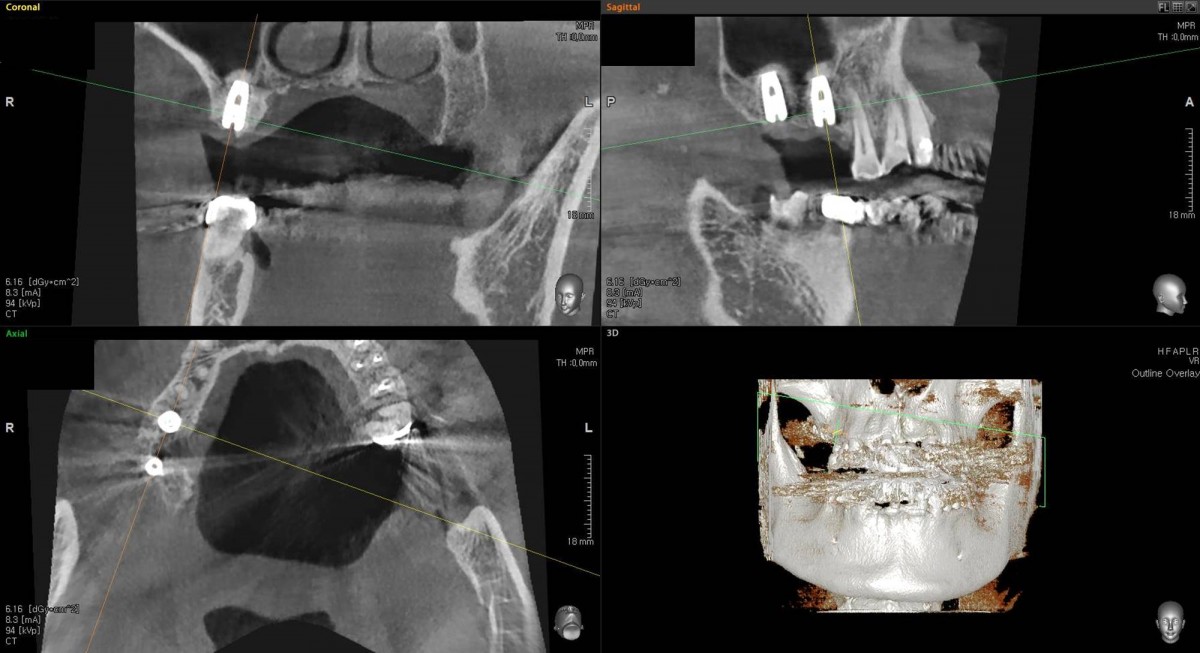

Socket Lift and Implant Placement in the right maxilla.

<GCacg> A 56-year-old male patient complained of pain in the right upper and lower jaws. And he wanted the upper first molar to be pulled out first.